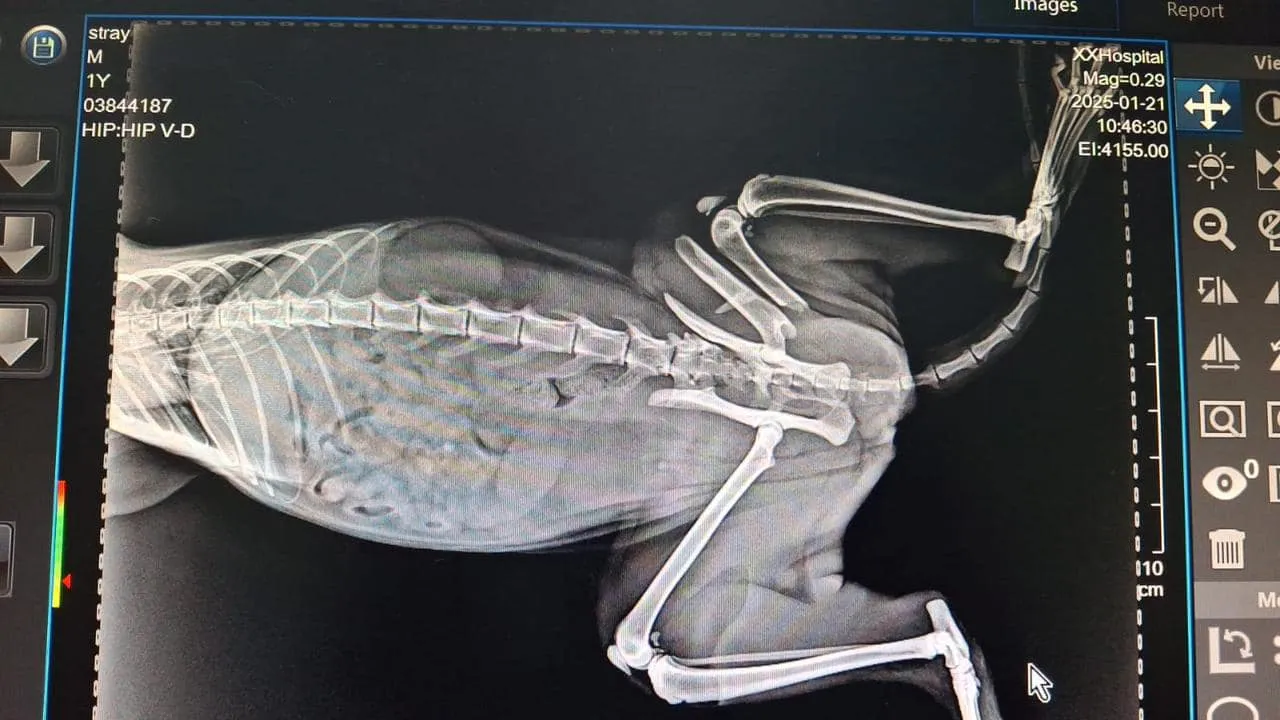

A surgical procedure for a pelvic fracture in cat